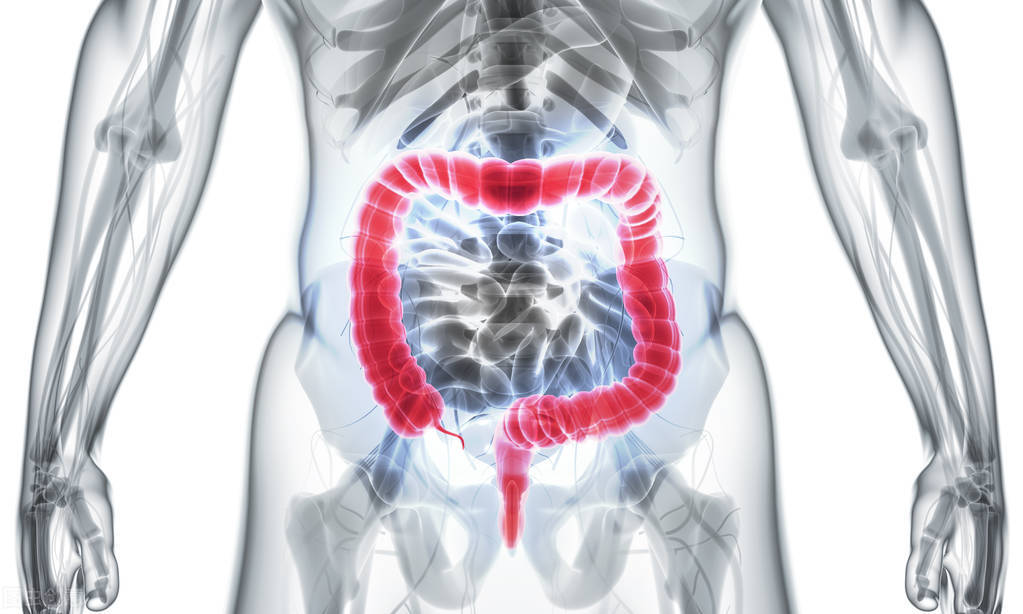

先给大家介绍一下解剖学上结肠和直肠的位置在哪里。首先我们看下面这张人体消化系统的示意图。我们按照食物的消化路径来给大家介绍结肠和直肠的位置。我们最先看到的是胃部分,此处是食物消化分解的地方,然后分解后的食物会被释放到小肠,在小肠中食物中的大部分营养物质都被吸收。小肠连接着大肠(也称为结肠),被吸收完营养物质的食物来到大肠后,大肠从食物中吸收水和矿物质,存储废物。最后废物移动到直肠,此处是消化系统的最后6英寸位置,后通过肛门排出体外。因此这个顺序简单总结为胃→小肠→大肠→直肠→肛门。通常大家所说的大肠,在医学上就是指结肠,为M字型(见下图)。结肠根据位置划分由4个区域组成,分为升结肠、横结肠、降结肠和乙状结肠。现在大家顺着我们的指示,来看结肠这4个区域分别在哪里。结肠从盲肠连接开始,向上延伸后为升结肠部分;然后向左横跨整个部分为横结肠部分;接着向左下腹下降为降结肠部分,最后连接乙状结肠,然后到直肠、肛门。